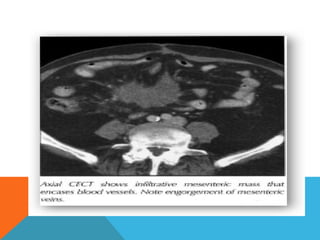

Mesentry And Omentum

 Infiltration and thickenining of mesentry

 Omental caking

 Nodular or strand like soft tissue density

 Calcified foci

 Rounded mass